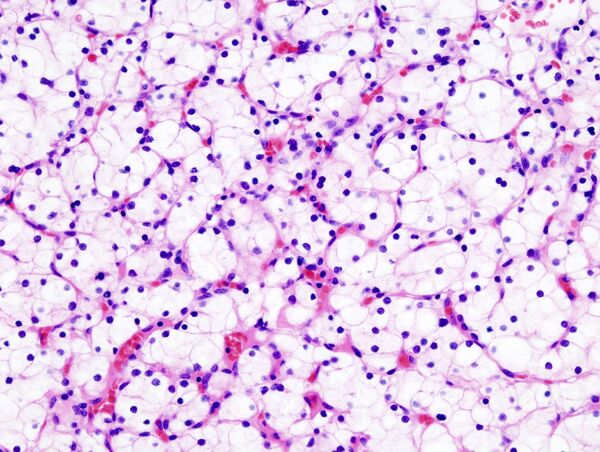

Ранее рак почки классифицировали по типу клеток и характеру роста. Позже было установлено что рак почки в абсолютном большинстве — смешанный. Современная классификация основывается на морфологических, цитогенетических и молекулярных исследованиях, а также иммуногистохимическом анализе и выделяет 5 видов почечно-клеточного рака[34]:

- светлоклеточный рак почки

Папиллярный почечно-клеточный рак при этом включает два отдельных подтипа: 1-й из них представлен мелкими клетками со светлой цитоплазмой, 2-й — крупными клетками и эозинофильной цитоплазмой (для данного подтипа вероятность развития метастазов выше)[16].

В рамках упоминавшегося выше многоцентрового кооперированного исследования 2012 года гистологический тип опухоли почки после операции был описан у 7357 из 7813 больных раком почки, присутствовавших в базе данных. При этом светлоклеточный вариант рака был выявлен у 6774 (92,1 %) пациентов, папиллярный — у 303 (4,1 %), хромофобный — у 175 (2,4 %), рак собирательных трубочек — у 17 (0,2 %), а наличие саркомоподобного рака в опухоли отмечалось у 88 пациентов. Частота выявления светлоклеточных и несветлоклеточных форм почечно-клеточного рака заметно отличалась от данных, полученных в начале 2000-х гг. в зарубежной клинической практике (где на долю светлоклеточного варианта приходилось 80—90 % злокачественных опухолей, папиллярного — 10—15 %, хромофобного — 4—5 %, рака из собирательных трубочек — менее 1 %, а 7 % случаев осталось неклассифицированными[16]); это, возможно, связано с определённой недооценкой частоты хромофобного и особенно папиллярного вариантов, допускаемой российскими морфологами[33].